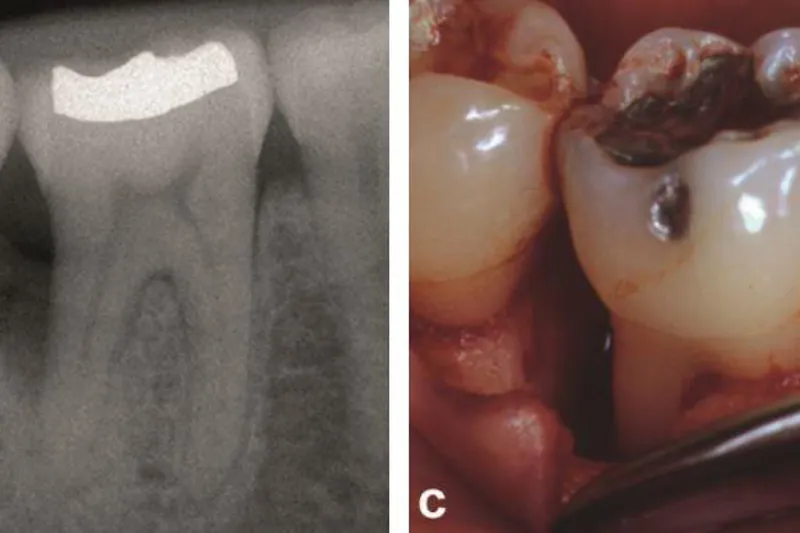

151 patienter med en gennemsnitsalder på 56 år, heraf 31 over 65 år, indgik i studiet. Der blev udført regenerativ kirurgi med EMD på i alt 253 parodontale defekter, heraf 44 furkaturinvolveringer. Patienterne blev undersøgt klinisk og radiologisk ved forsøgets start samt efter et og tre år. Patienterne fik professionel tandrensning og støttebehandling hver måned de første seks måneder og hver tredje måned igennem resten af forløbet.

Gennemsnitsværdierne for pochedybde, fæstetab og radiologisk knogletab var ved forsøgets start henholdsvis 6,14 mm, 7,22 mm og 5,08 mm. Der blev fundet signifikante forbedringer af alle tre parametre efter både et og tre år (pochedybde 2,84 mm og 2,87 mm; fæstetab 2,40 mm og 2,47 mm; knogletab 1,76 mm og 2,39 mm).